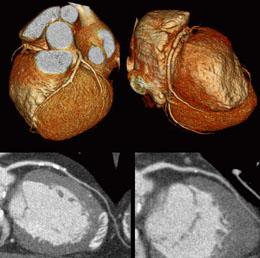

August 23, 2010 - Two companies recently signed a strategic partnership agreement drawing on both firms' established expertise in imaging technology to establish computed tomography (CT) as a viable, minimally-invasive imaging alternative for many cardiovascular procedures.

GE Healthcare and medical imaging company Arineta Ltd., entered into a partnership to develop new computed tomography (CT) angiography solutions in an effort to address issues with cost, access and quality of cardiac care.